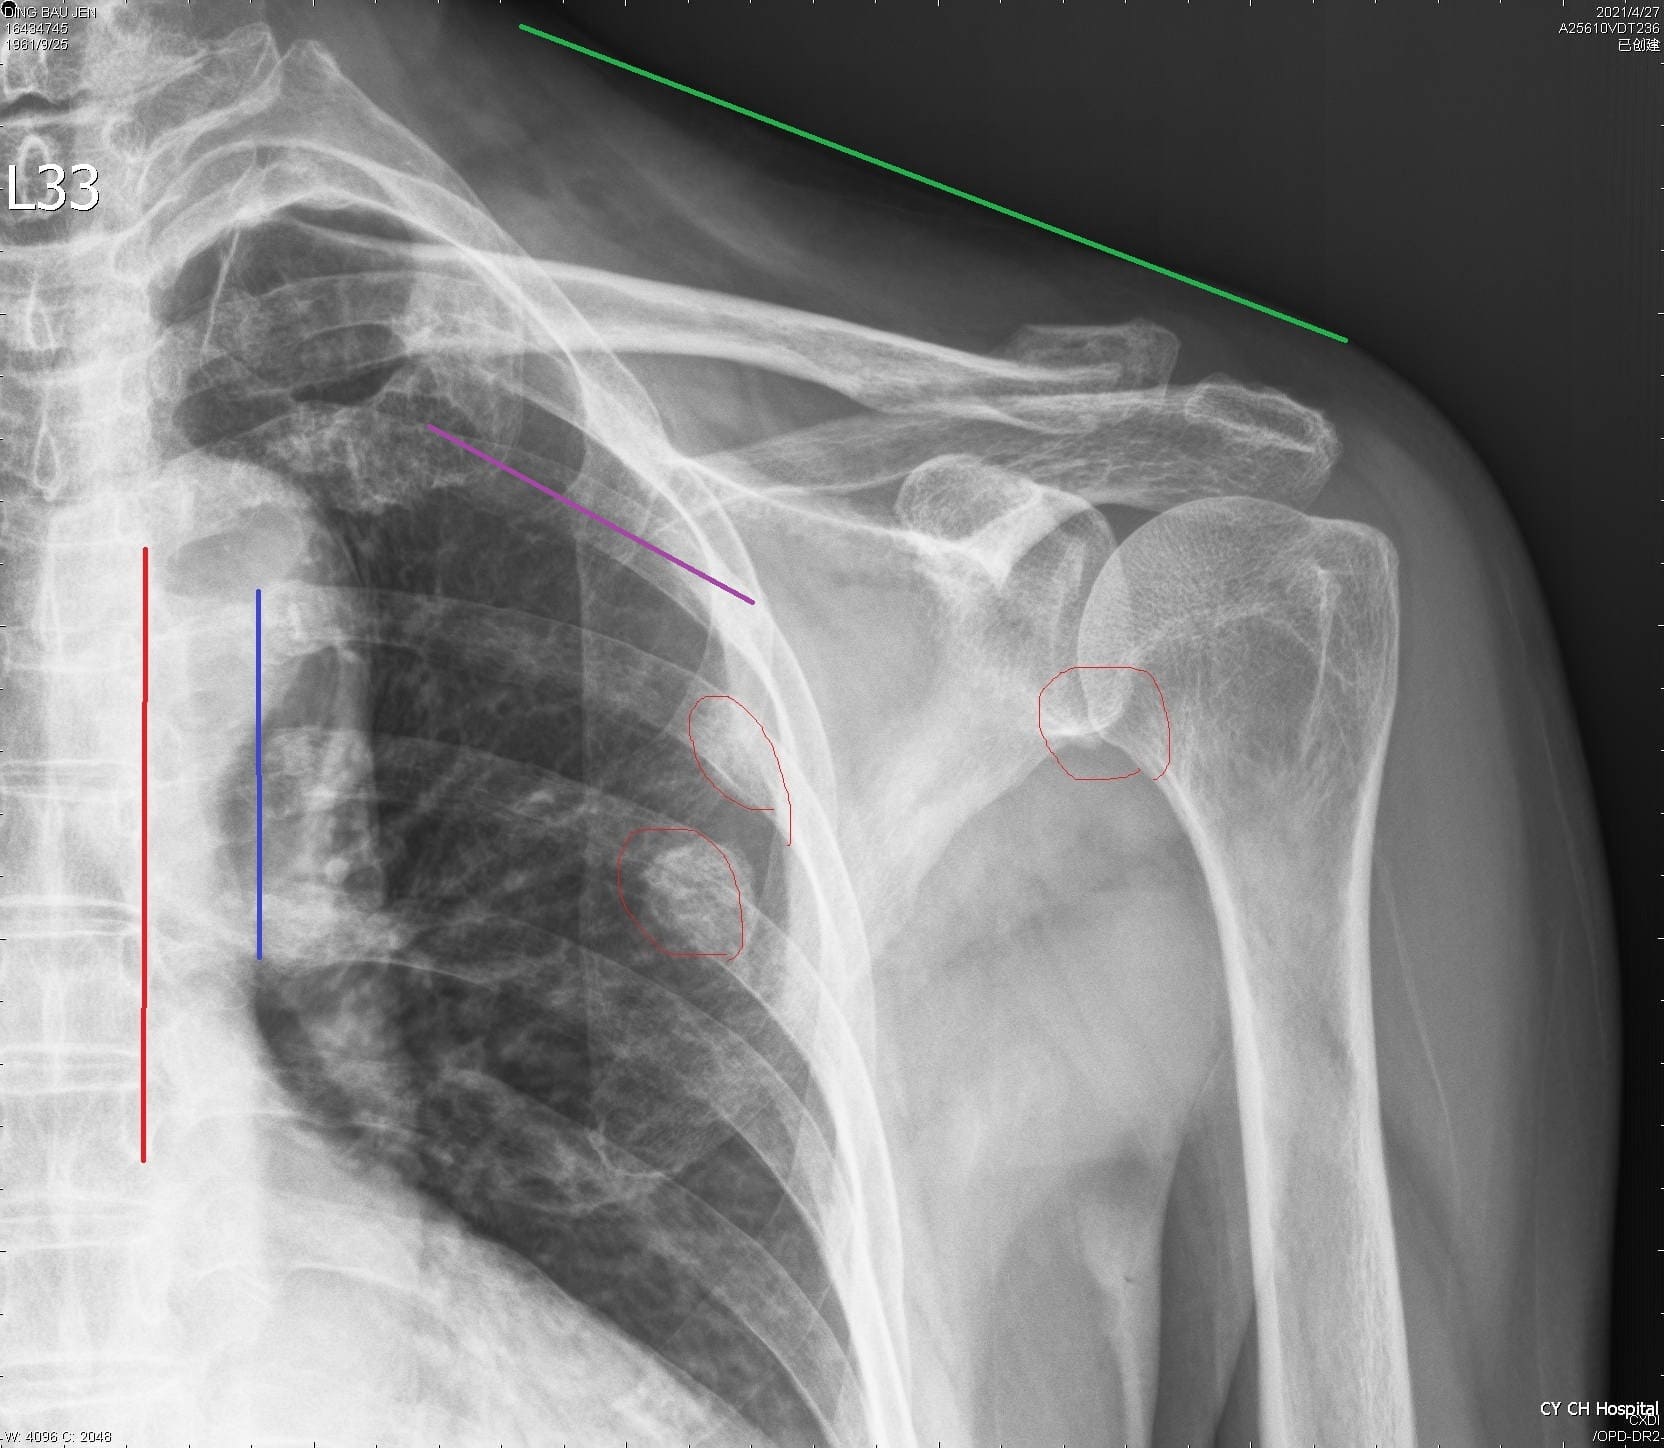

車禍肋骨與四肢骨折 無創傷手術